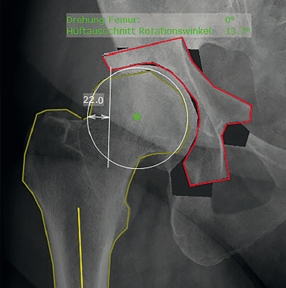

4. Đo đạc và đánh giá hình thái giải phẫu khớp háng một cách chuyên nghiệp với chức năng phân tích hội chứng "F.A.I"

Để nghiên cứu mối liên quan giữa các đặc điểm hình thái tổng thể của hông và phạm vi chuyển động ở những bệnh nhân có tật và những bệnh nhân không có triệu chứng (những bệnh nhân khỏe mạnh có các đặc điểm chụp X quang đặc trưng cho FAI).

6. Xác định chênh lệch offset của ổ cối hai bên

Mức độ chính xác của cỡ số ổ cối theo tỷ lệ phóng đại X quang từng trường hợp . Đánh giá mức độ chính xác của cỡ số ổ cối theo tỷ lệ phóng đại trung bình. Khoảng chênh lệch từ tâm xoay đến đường thẳng đứng đi qua góc dưới xương ổ cối cùng bên so với bên lành.